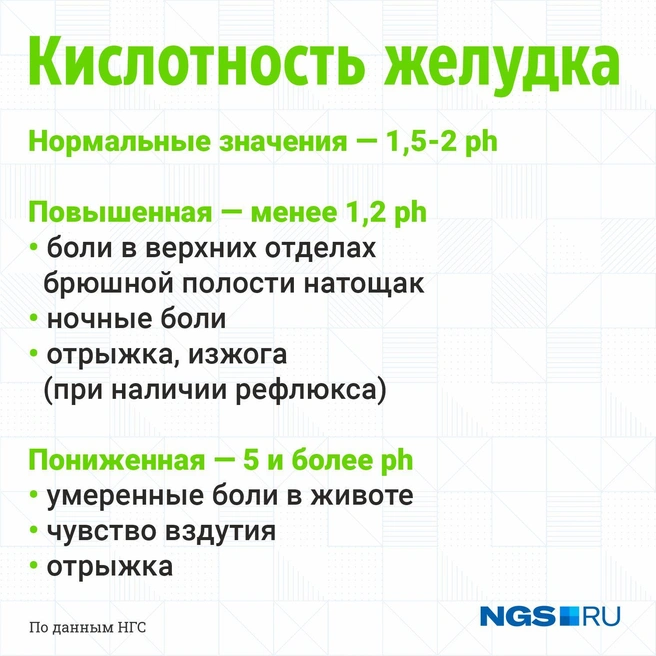

Измерение кислотности желудка проводится в условных единицах — pH. В норме этот показатель составляет 1,5–2 pH. Если желудочно-кишечный тракт окажется в патологическом состоянии, показатель кислотности желудка изменится.

Ph менее 1,2 — это состояние повышенной кислотности, следствие нарушенных процессов кислотопродукции и кислотонейтрализации.

— Это состояния, предшествующие возникновению эрозий или язв желудка и двенадцатиперстной кишки. Основные симптомы — боли в верхних отделах брюшной полости натощак, ночные боли — со снижением интенсивности или исчезновением после еды. При наличии рефлюкса часто отмечается отрыжка, изжога, — описывает Татьяна Мамаделеева.

Ph 5 и более — состояние пониженной кислотности. Оно возникает из-за атрофии слизистой оболочки желудка и не так ярко проявляется клинически.

— Чаще это умеренные боли в животе, чувство вздутия, отрыжка. Атрофические клетки при отсутствии соляной кислоты могут достаточно часто перерождаться в злокачественные клетки. Возникает рак желудка. К сожалению, это до сих пор очень распространенное онкологическое заболевание. Уверенно входит в пятерку самых частых онкопатологий. Лечится только хирургическим путем, практически не поддается лучевой и химиотерапии, — поясняет Татьяна Мамаделеева.